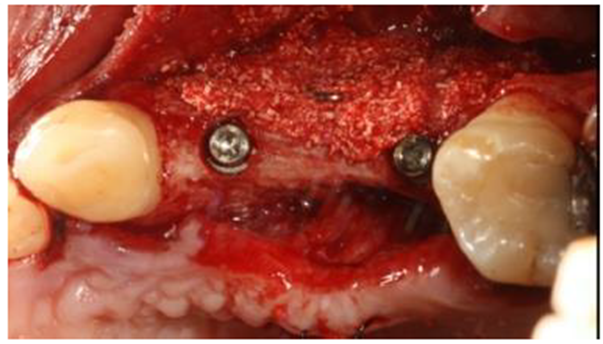

O espaço criado pelo parafuso foi preenchido com osso inorgânico bovino associado à fibra colágena bovina na proporção de 75/25 (Extra Graft XG-13 – Implacil De Bortoli – São Paulo – Brasil). O retalho foi fechado cobrindo o material sem a adição de membranas (Figura 8).

Após seis meses, os implantes foram reabertos e foi observado osso neoformado pelo material até o nível do parafuso, corrigindo o defeito em espessura e mantendo uma parede óssea vestibular espessa suficiente para manter o implante em função (Figura 9).